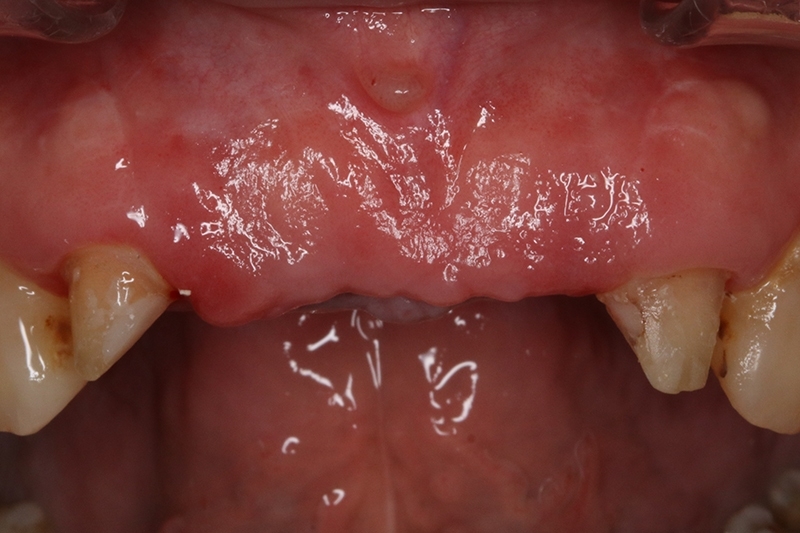

經過牙周治療後,控制發炎,可見牙齦的狀況變得更健康了!

初步等待2個月軟組織癒合,再來進行垂直脊水平骨牙脊增寬術,使用不可吸收再生膜Cytoplast 及迷你骨釘 Tack固定放置的人工骨粉。